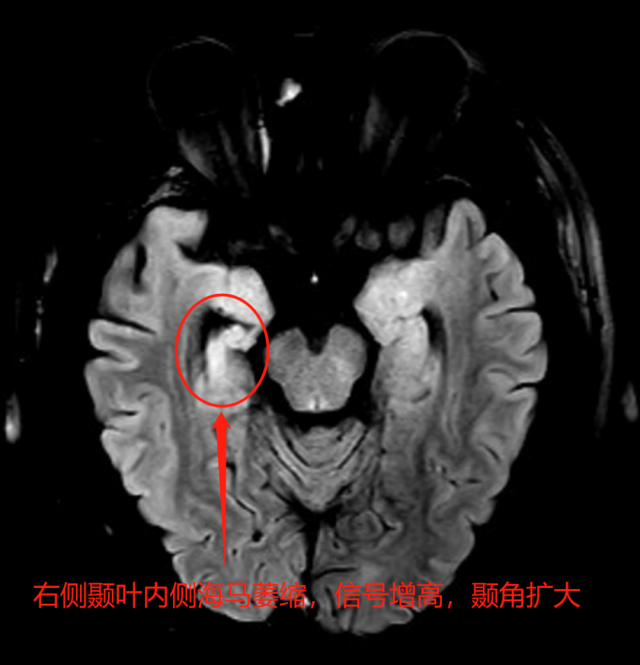

头颅癫痫序列磁共振:右侧海马萎缩并硬化